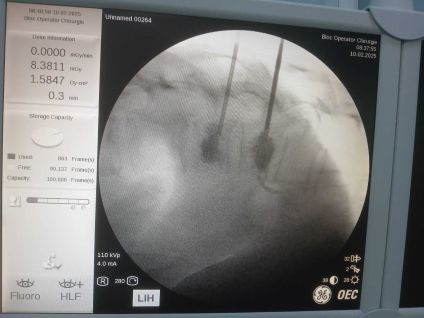

În data de 10 februarie 2025, la Spitalul Județean de Urgență Buzău a avut loc o intervenție neurochirurgicală în premieră. Este vorba despre o intervenție de vertebroplastie percutană, sub control radiologic.

În premieră la nivelul județului Buzău, s-a intervenit neurochirurgical prin procedura denumită „vertebroplastie percutană sub control radiologic”. Operația a durat 30 de minute iar pacienta s-a recuperat complet, cu externare în aceeași zi, post procedural.